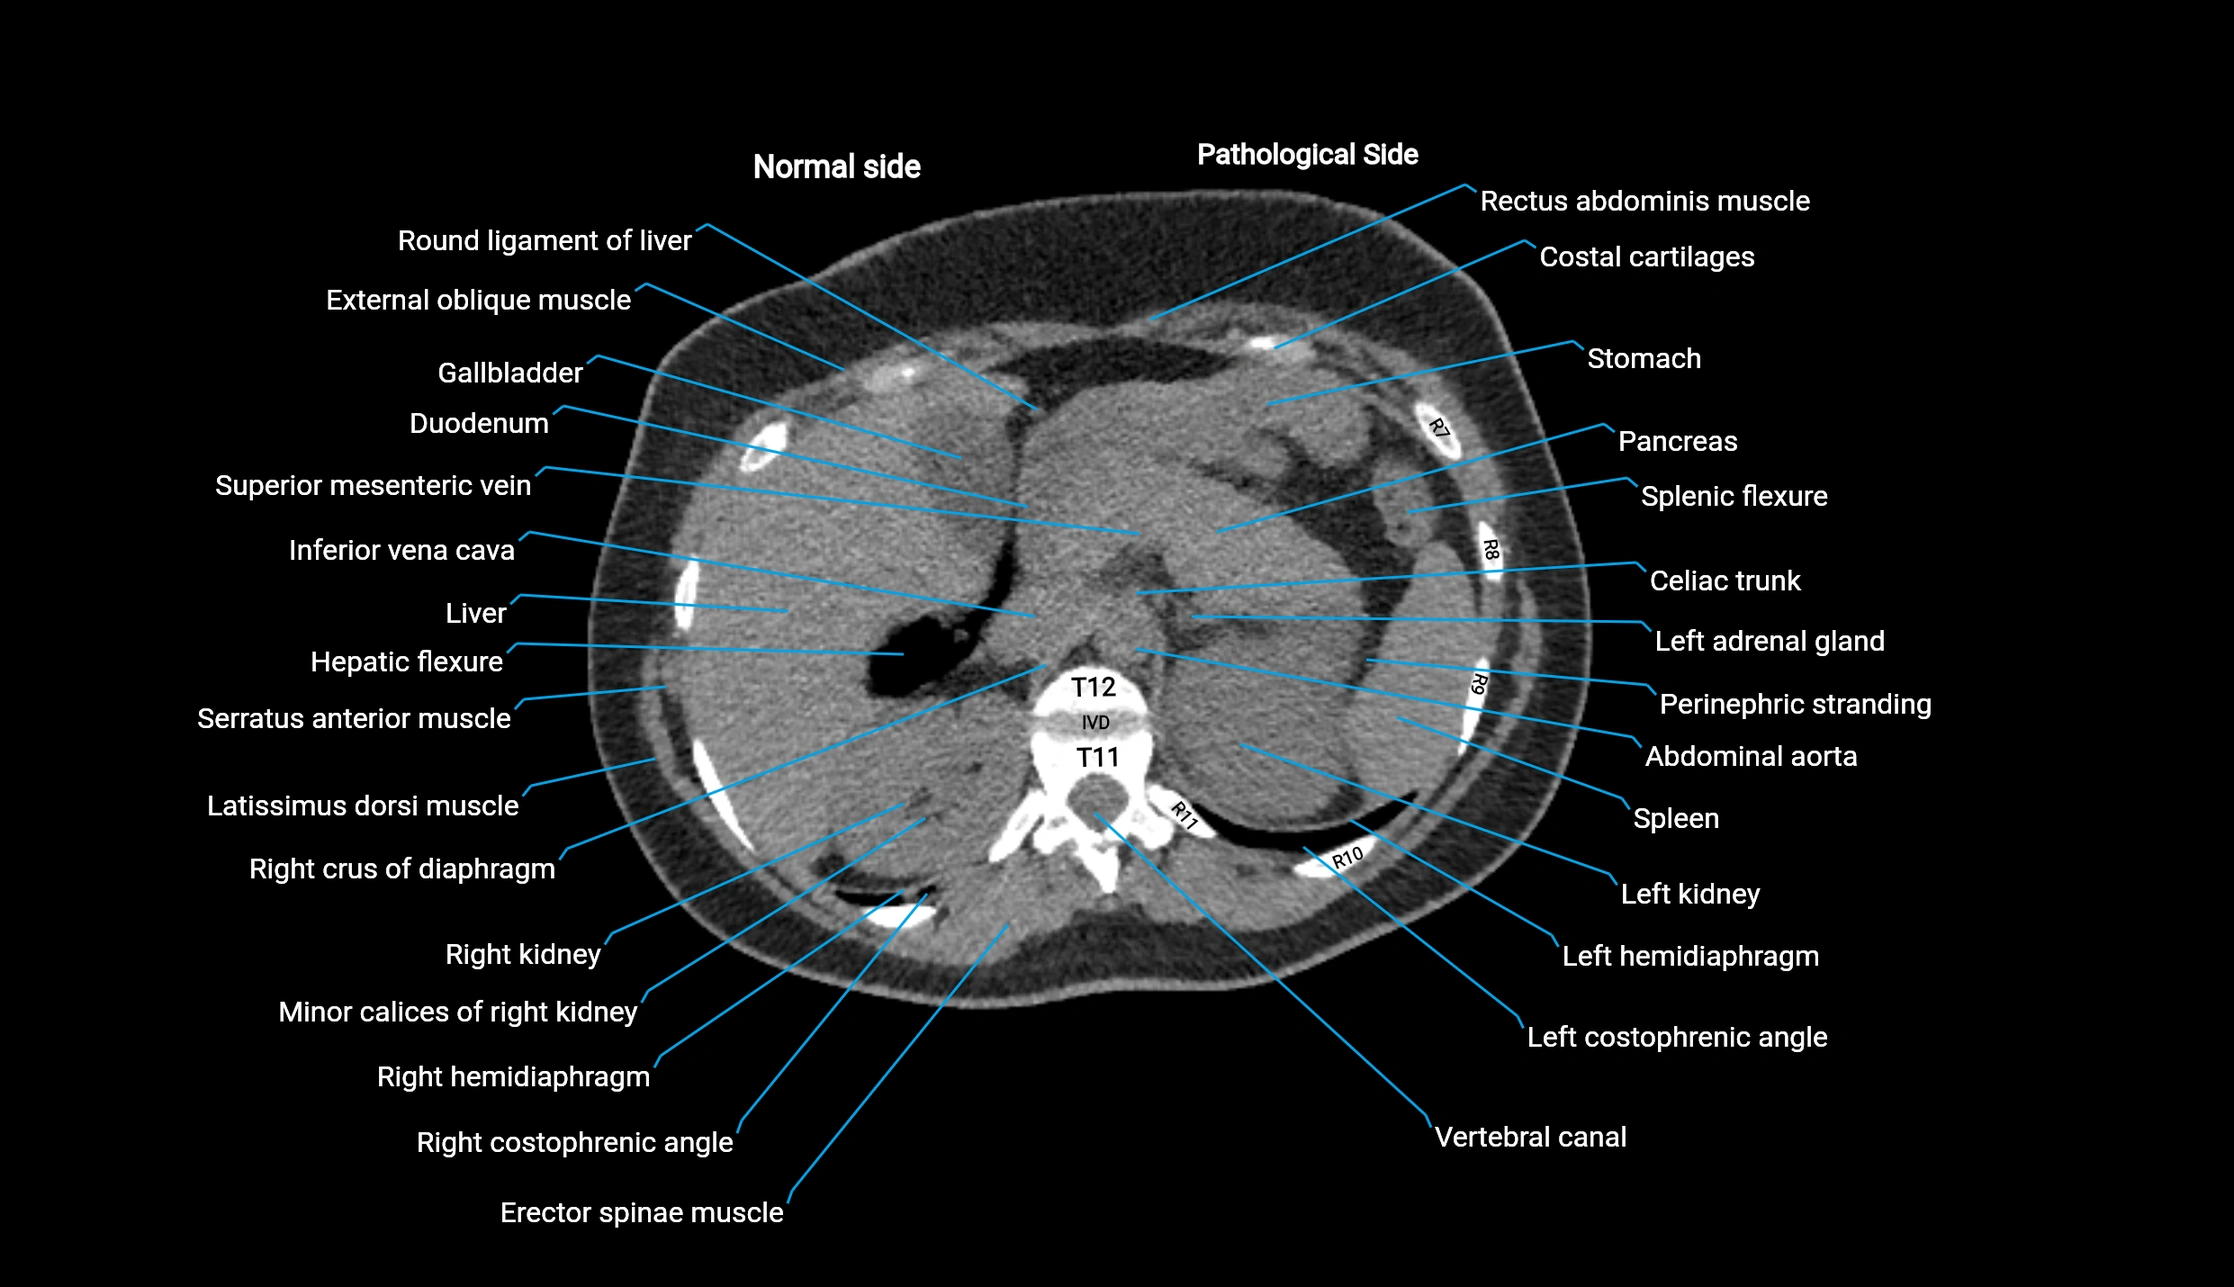

CT image

image